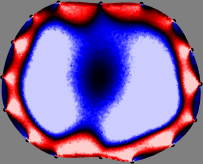

Refer to caption

Figure 2: Fidelity-embedded regularization method. (Left bottom) Correlations between four different column vectors (𝐒ksubscript𝐒𝑘{\bf S}_{k}) and all the remaining column vectors (𝐒subscript𝐒{\bf S}_{\ell}) are visualized. (Right bottom) Performances of the proposed fidelity-embedded regularization method for λ=𝜆\lambda=\infty are shown by numerical simulations.

To explain the FER method, we closely examine the correlations among column vectors of the sensitivity matrix 𝕊𝕊\mathbb{S}, described in Fig. 2. The correlation between 𝐒ksubscript𝐒𝑘{\bf S}_{k} and 𝐒subscript𝐒{\bf S}_{\ell} can be expressed as

for i=1,,16𝑖116i=1,\cdots,16[23]. This shows that the column vector 𝐒ksubscript𝐒𝑘{\bf S}_{k} is like an EEG (electroencephalography) data induced by dipole sources with directions uj,j=1,,16formulae-sequencesubscript𝑢𝑗𝑗116\nabla u_{j},j=1,\cdots,16 at locations ΔksubscriptΔ𝑘\Delta_{k}. Given that two dipole sources at distant locations produce mutually independent data, the correlation between 𝐒ksubscript𝐒𝑘\mathbf{S}_{k} and 𝐒subscript𝐒\mathbf{S}_{\ell} decreases with the distance between ΔksubscriptΔ𝑘\Delta_{k} and ΔsubscriptΔ\Delta_{\ell}. Fig. 2 shows a few images of the correlation 𝐒k,𝐒(|𝐒k||𝐒|)1subscript𝐒𝑘subscript𝐒superscriptsubscript𝐒𝑘subscript𝐒1\left\langle\mathbf{S}_{k},\mathbf{S}_{\ell}\right\rangle(|\mathbf{S}_{k}||\mathbf{S}_{\ell}|)^{-1} as a function of \ell for four different positions ΔksubscriptΔ𝑘\Delta_{k}. The correlation decreases rapidly as the distance increases. In the green regions where the correlation is almost zero, 𝐒subscript𝐒{\bf S}_{\ell} is nearly orthogonal to 𝐒ksubscript𝐒𝑘{\bf S}_{k}.